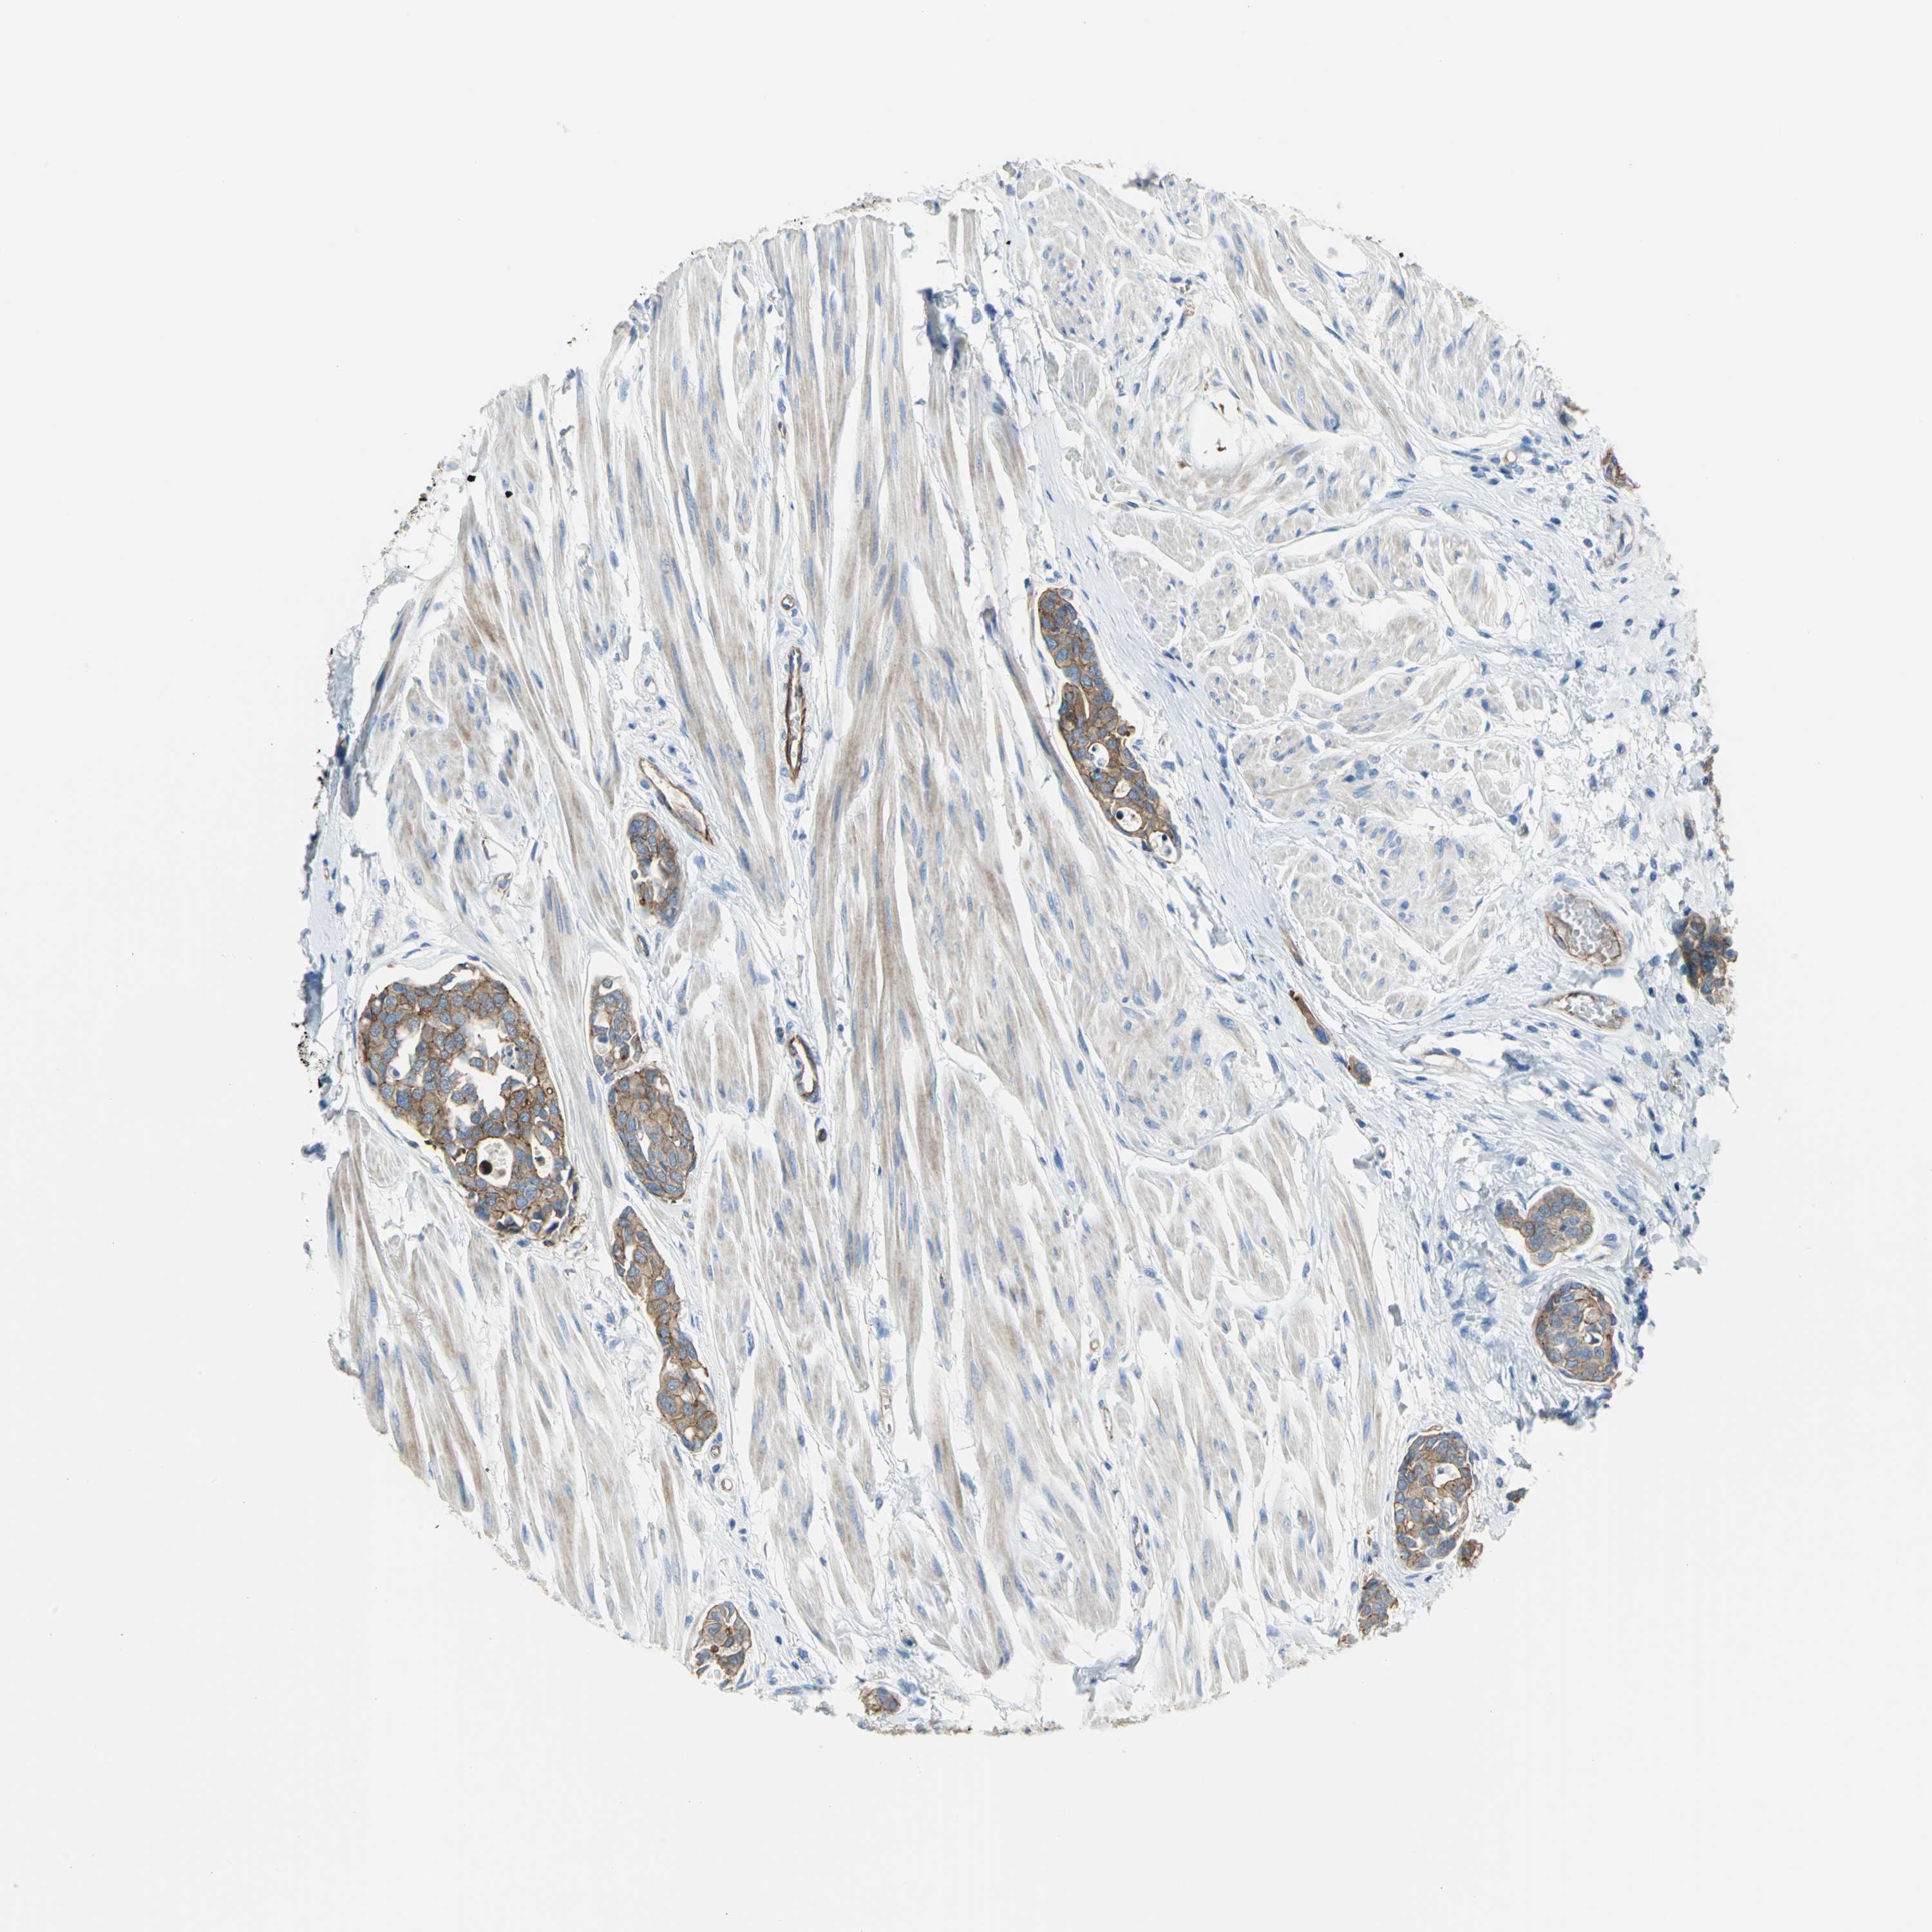

UROTHELIAL CANCER - Protein expressioni

A mouse-over function shows sample information and annotation data. Click on an image to view it in a full screen mode. Samples can be filtered based on level of antibody staining by selecting one or several of the following categories: high, medium, low and not detected. The assay and annotation is described here.

Note that samples used for immunohistochemistry by the Human Protein Atlas do not correspond to samples in the TCGA dataset.

Antibody stainingi

Antibody staining in the annotated cell types in the current human tissue is reported as not detected, low, medium, or high, based on conventional immunohistochemistry profiling in selected tissues. This score is based on the combination of the staining intensity and fraction of stained cells.

Each image is clickable and will lead to virtual microscopy that enables deeper exploration of all samples and also displays staining intensity scores, fraction scores and subcellular localization as well as patient and tissue information for each sample.

Antibody HPA004747

Antibody HPA004886

Antibody CAB019322

Staining

High

Medium

Low

Not detected

Intensity

Strong

Moderate

Weak

Negative

Quantity

>75%

75%-25%

<25%

None

Location

Nuclear

Cytoplasmic/membranous

Cytoplasmic/membranous,nuclear

Urothelial carcinoma, High grade

Urothelial carcinoma, Low grade